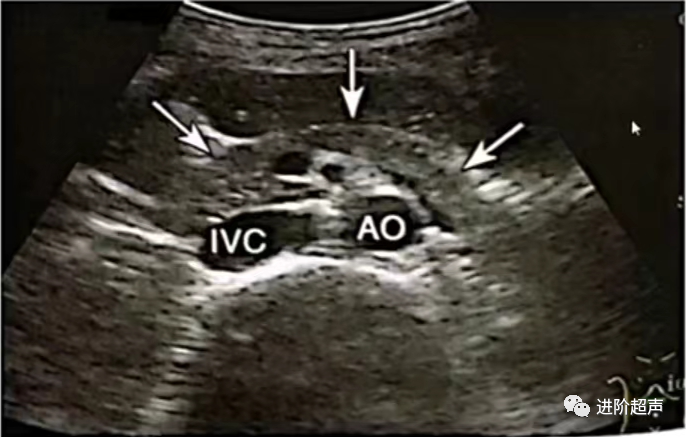

正常胰腺切面扫查

胰腺的长轴切面,胰头、颈、体、尾部的短轴切面,以及左肋间通过脾窗的胰尾切面

胰腺前后径测量(胰腺长轴切面)和胰管测量:

胰头前后径

下腔静脉前、胰腺后缘中点向前的垂直线

胰体前后径

腹主动脉和肠系膜上动脉圆心连线通过胰体前后缘的距离

胰尾前后径

过腹主动脉圆心,并和上述两圆心相交呈45°的直线上取胰尾前后缘距离

胰管

胰管显示最宽处

正常胰管内径(前后径)体部不大于2mm

头颈部不大于3mm

显示胰腺长轴灰阶图像1张

胰腺长轴灰阶图像 (箭头所示)

IVC:下腔静脉 AO:腹主动脉